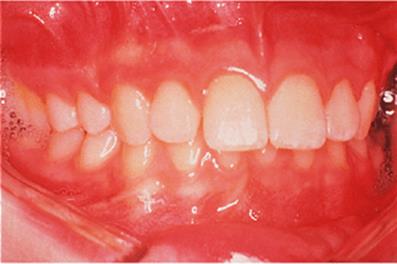

The appliance holds the mandible in a forward postured position, in this case with the incisors edge to edge (Fig. 18.1(f)). The facial musculature is thus stretched, and applies a posterior force to the upper arch and an anterior force to the lower arch. The lower incisors have acrylic capping to prevent excessive labial tilting of the lower incisors, and this also serves as a bite-plane to reduce the overbite (Chapter 10). The appliance must be worn for at least 14–16 hours each day, but once the overjet has been reduced fully the amount of daily wear can gradually be reduced to sleeping hours only. The patient should continue to wear the appliance overnight in this way as a retainer, at least until the period of rapid pubertal growth is complete. Figures 18.1(g) and 18.1(h) show the dental and facial changes which occurred during treatment.

Fig. 18.1. (a) This 12-year-old girl had a skeletal II facial pattern and average facial proportions. The lips were incompetent with the lower lip lying below the upper incisors at rest. (b), (c) She had a Class II division 1 malocclusion with an overjet of 10 mm, the overbite was increased and complete, and the molar relationship was Class II on both sides. (d), (e) The upper and lower arches were well aligned. (f) A functional appliance (an activator) was fitted. (g) The corrected occlusion with Class I incisor and molar relationships. (h) The patient's facial profile at the end of treatment.